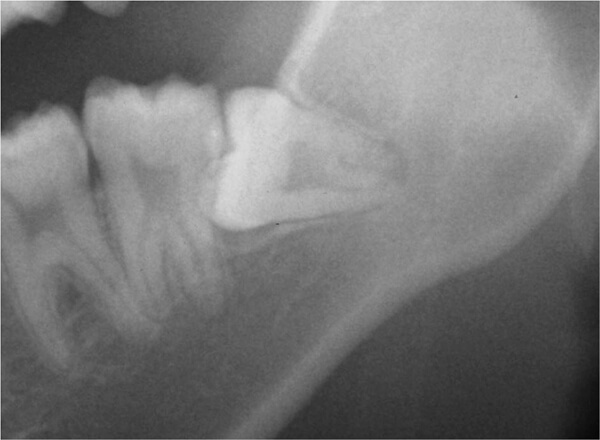

③下顎垂直埋伏智歯

下顎の智歯(親知らず)が骨に埋まっている状態。